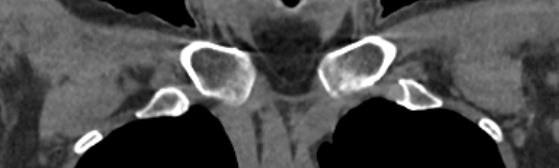

Однако классический рентген не всегда обеспечивает качественную визуализацию ГКС из-за наложения друг на друга изображений костных структур. Компьютерная томография лишена таких недостатков. При проведении КТ излучатель рентгеновских лучей совершает круговые движения вокруг исследуемой области, проводя сканирование в различных плоскостях. В результате получаются детальные снимки высокого качества, а после цифровой обработки – трехмерные модели грудино-ключичных сочленений в мельчайших подробностях.

КТ благодаря быстроте, доступности и высокой информативности часто назначается в экстренных ситуациях, например, при травмах и в случае необходимости проведения оперативного лечения. Поэтому метод особенно востребован в ортопедии и травматологии. На снимках КТ и трехмерных изображениях можно оценить состояние суставных поверхностей грудино-ключичных сочленений, а в случае перелома определить точную локализацию костных отломков.